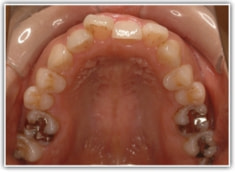

治療後(2年後)